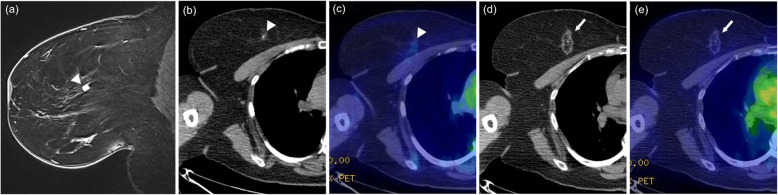

Fig. 2.

Fatty mass type. A 55-year-old woman with invasive ductal carcinoma. Breast magnetic resonance imaging (MRI) before cryoablation (a, arrowhead) showing a solid nodule of diameter 8 mm in the inner-upper quadrant of the right breast. The pre-cryoablation CT part of PET/CT (b, arrowhead) does not clearly show the breast cancer lesion identified by MRI. The pre-cryoablation fusion image of PET/CT (c, arrowhead) shows subtle FDG uptake (SUVmax, 0.89). On the CT portion (d, arrow) and (e, arrow) of the fusion image of PET/CT that was obtained 36 months after cryoablation, the treated area shows a focal fatty area surrounded by a rim like soft tissue density with subtle FDG uptake (SUVmax, 0.82). The calcification at the center of the treated area was present prior to cryoablation